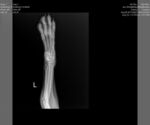

Dog Breed: Boxer (short coat). Adoption Fee: $427.50 includes all applicable MN sales tax. Ricky Bobby has a broken left front leg that will require surgical repair. He will not be available for adoption until after surgery and some recovery time. We are working on getting the surgery scheduled between Aug 25th-Sept 5th. This adorable boy has all of his routine vetting done but still needs to be neutered. He is housebroken and crate trained. Ricky Bobby is wonderful with other dogs and with kids and doesn't seem to bother cats. ***NOT ACCEPTING APPLICATIONS FOR RICKY BOBBY AT THIS TIME*** 9/12 UPDATE: Ricky Bobby had surgery to repair his broken leg yesterday and did amazing!!!